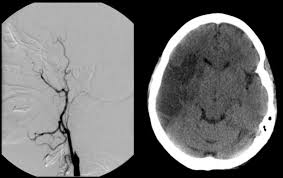

This article will focus on the cause of neck instability causing pressure on the nerves, arteries and veins that run through the cervical spine and into the. Besides musculoskeletal and nerve conditions, other causes of neck pain include cervical artery dissection, meningitis, infections localized to tissues. Headache or neck pain is a frequent symptom of spontaneous cervical artery dissection (scad). Whiplash associated disorders and neck rehabilitation online course: · the neck pain from a carotid artery tear often spreads along the side of the neck and up toward the outer corner of the eye. Had an ultrasound done on both the caratid arteries and no plaquing was evident. A major blood vessel called the vertebral artery also runs alongside the vertebrae to carry blood to the rear (posterior) part of your brain. Severe headache, fever, scalp tenderness, jaw pain, vision.

Discover 10 common causes of neck pain at 10faq health and stay better informed to make healthy living decisions. If you do, try to take breaks often and move your neck in other directions to keep your muscles loose. The pain comes and goes. answered by dr. You can read more about carotid artery disease here. Pain is in neck, jaw, ear, and temple areas. The pain may just be a mild nuisance, or it could be so excruciating that a person avoids any excessive movement. But in some cases the pain becomes constant or radiates vertebral arteries (arteria vertebralis) next to your spine which become basilar artery (arteria basillaris) and brings blood to the back of the brain. Although its pathophysiology and treatment closely resemble that of its sister condition, carotid artery dissection (cad), the clinical presentation, etiology, and epidemiological profile of vads.

Neck pain (cervical pain) may be caused by any number of disorders and diseases. It radiates into my jaw, shoulder and right arm. What can cause one sided frontal neck pain? But beyond good old aging, the causes of neck pain are as varied as the list is long. There are seven vertebrae that are the bony building blocks of within the neck, structures include the neck muscles, arteries, veins, lymph glands, thyroid gland, parathyroid glands, esophagus, larynx, and trachea. The pain may just be a mild nuisance, or it could be so excruciating that a person avoids any excessive movement. Early presentation of cervical artery dissection can be very subtle and overlaps with more common causes of headache and neck pain like tension headache or musculoskeletal neck pain. Oftentimes neck pain is located in one spot and goes away on its own within a few days or weeks. If you do, try to take breaks often and move your neck in other directions to keep your muscles loose. A cervical artery dissection is a tear in one of the arteries in the neck that carry blood to the brain. Harinder gill pain & lump: But in some cases the pain becomes constant or radiates vertebral arteries (arteria vertebralis) next to your spine which become basilar artery (arteria basillaris) and brings blood to the back of the brain. Oftentimes neck pain is located in one spot and goes away on its own within a few days or weeks.